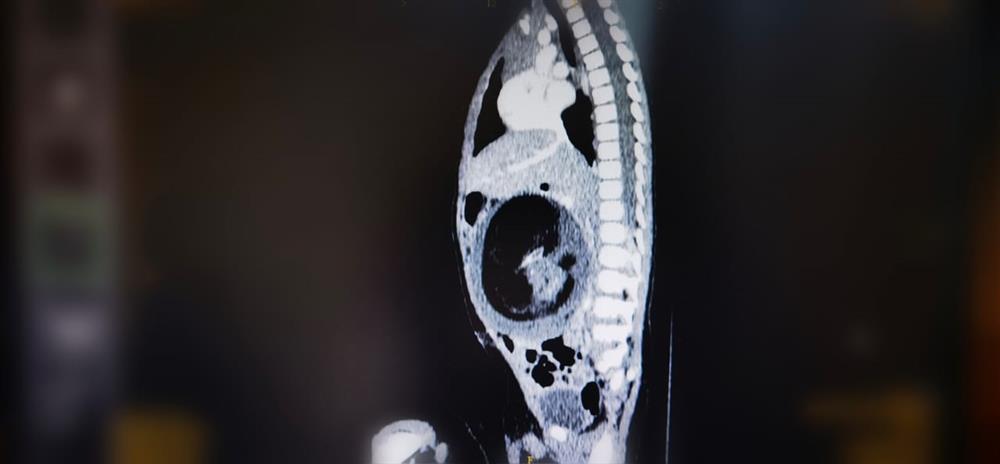

صورة مقطعية للحالة النادرة التي يظهر فيها جنين داخل جنين قبل الولادة (وكالة الأنباء العمانية)

في حالة طبية جراحية نادرة على مستوى العالم، تمكن قسم جراحة الأطفال بالمستشفى السلطاني بعُمان، من إجراء جراحة نادرة، تمثلت في استئصال جنين من داخل جنين، لطفل يبلغ من العمر ثمانية أشهر، سُمح له بمغادرة المستشفى بعد ثلاثة أيام من إجراء الجراحة، والتحقق من الفحوص والمؤشرات التي أثبتت نجاح العملية، على الرغم من الظروف الاستثنائية للحالة.

وتوصف الحالة طبياً بأنها عيب خُلقي تتكون فيه كتلة من الأنسجة تشبه الجنين داخل الجسم، وهناك نوعان من نظريات المنشأ في شأن الحالة، إحداها تعتبر أن الكتلة تبدأ كجنين طبيعي، ولكنها تتحول إلى مغلف داخل توءمه، والأخرى تعتبر أن الكتلة هي ورم مسخي متطور للغاية، ويحدث بنسبة واحد لكل 500 ألف ولادة حية.